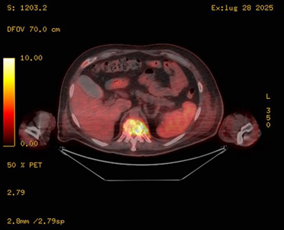

Given the presence of an intracardiac device and persistent MRSA bacteremia, both transthoracic and transesophageal echocardiography (TTE and TEE) were promptly performed. These showed no evidence of valvular vegetations or leadassociated infection. Nevertheless, the ongoing positivity of blood cultures raised concern for disseminated opportunistic infections. A contrast-enhanced full-body CT scan revealed multiple bilateral pulmonary nodules consistent with septic emboli (Figure 1), as well as a chronic right subdural hematoma and a hyperdense focus in the right frontal region. Whole-body 18F-FDG PET/CT (Figures 2,3) demonstrated no abnormal uptake at the pacemaker pocket or along the leads, but revealed increased metabolic activity in the D11 vertebral body (SUV max 12.9), and in the right talus, tarsal bones, and surrounding soft tissues of the lateral malleolus (SUV 7.8) findings suggestive of vertebral osteomyelitis (spondylodiscitis) and chronic osteomyelitis, respectively. Additionally, a reversed liver-to-spleen metabolic gradient (spleen SUV 5.4) was observed, likely reflecting reactive inflammatory changes.

Figure 4: Axial fused 18F-FDG PET/CT image at the thoracolumbar level showing increased FDG uptake at D11 vertebral body, consistent with spondylodiscitis. Inferiorly, partial visualization of the right ankle reveals focal hypermetabolic activity involving bone and soft tissue, suggestive of distal osteomyelitis.